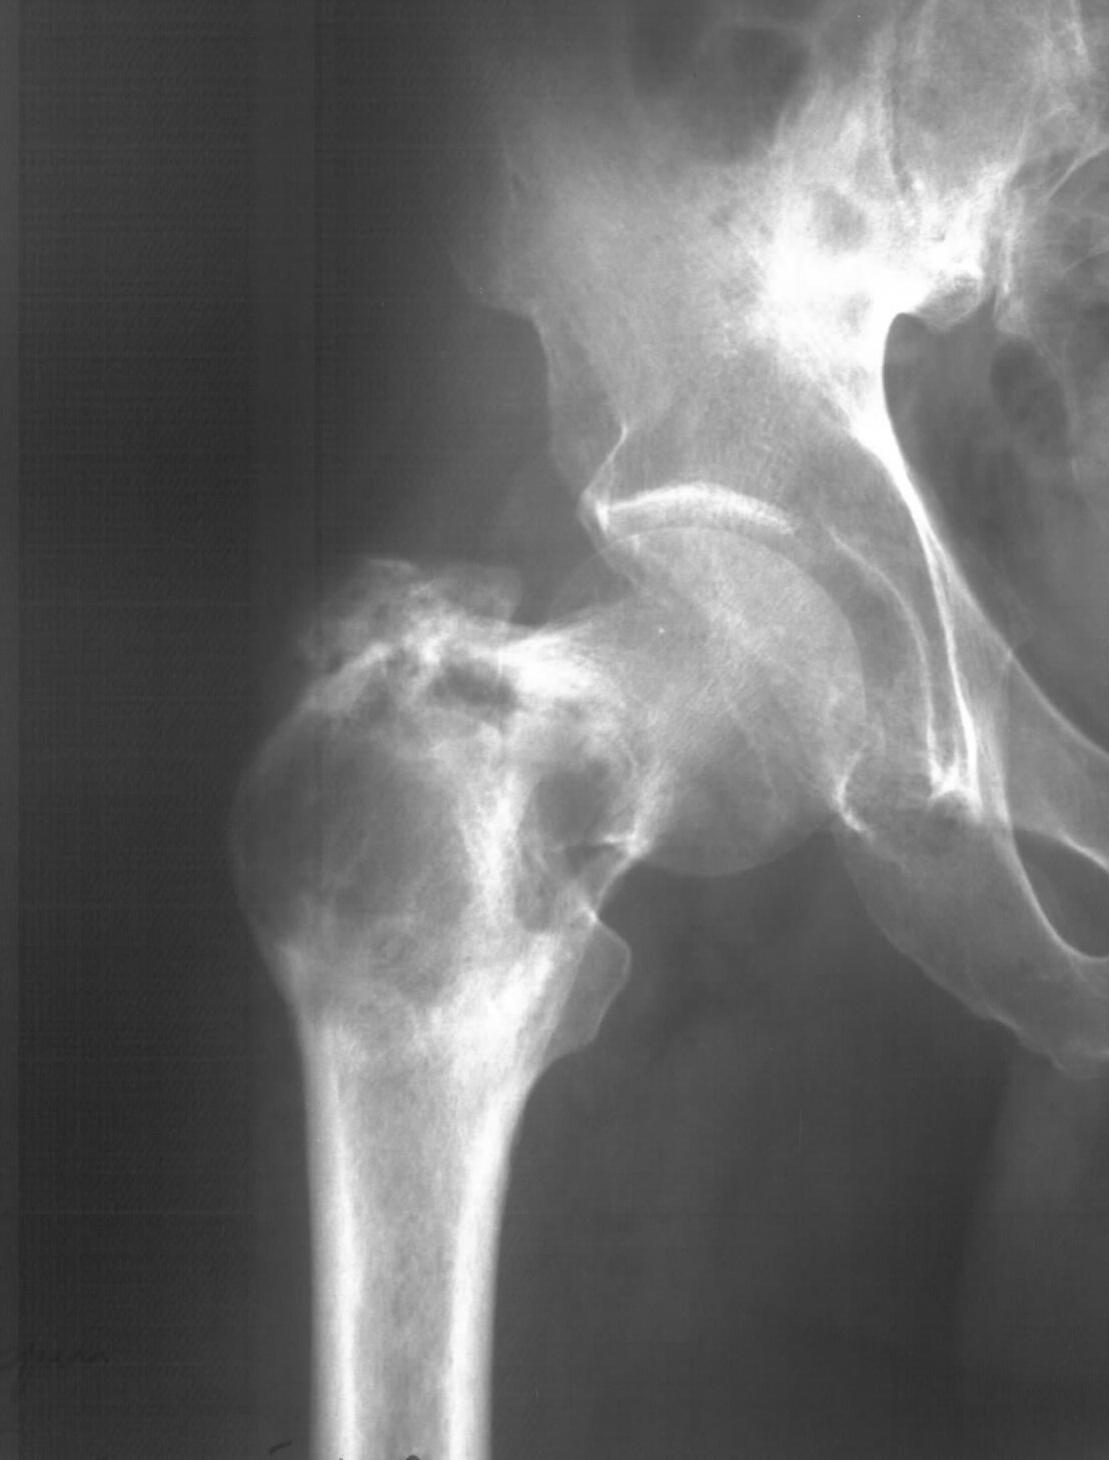

Диагноз: Ангиосаркома проксимального отдела правой бедренной кости. Патологический перелом шейки бедренной кости. Множественные метастазы в легкие, позвоночник, ребра, кости таза.

Считает себя больным с 2005 года, когда впервые появились боли в правом тазобедренном суставе с иррадиацией в поясничную область. Лечился по месту жительства по поводу поясничного остеохондроза, люмбоишиалгии. Отмечает постепенное усиление болей в области правого тазобедренного сустава. С августа 2007 года появилась хромота. В 2008 году была выполнена рентгенография тазобедренного сустава, выявлен патологический очаг в проксимальном отделе бедренной кости. Консультирован онкологом. Обследовался стационарно в травматолого-ортопедическом отделении №1 ГУЗ «СККЦ СВМП». Была выполнена операционная биопсия. Заключение: «наиболее вероятна картина гемангиоэндотелиомы с явлениями пролиферации и атипии». Для дальнейшего лечения был направлен в РОНЦ им. Н.Н.Блохина РАМН. Повторно была выполнена операционная биопсия с иммуногистохимическим исследованием материала. Заключение: «морфологическая картина более всего соответствует ангиосаркоме». Получил курс лучевой терапии. Планировалась повторная госпитализация для органосохраняющего оперативного лечения. Однако до настоящего времени госпитализация не состоялась.

31.05.09 упал дома с высоты собственного роста. Появились сильные боли в правом тазобедренном суставе. Самостоятельно обратился в ГУЗ «СККЦ СВМП». При клиническом обследовании и рентгенографии был диагностирован патологический перелом шейки бедренной кости.Объективно:

Интересно как онкологи оценивают вероятную подолжительность жизни, если более полугода, то наверное можно предложить биполярный онкологический протез. Для обсуждения не хватает снимков бедра на всю длину, и более подробной КТ ацетабулюма.

Судя по КТ опухоль кроме шейки захватила большой трохантер и частично головку бедра. На мой взгляд, даже самое удачное расположенние винтов гвоздя не позволит больному полностью наступать на ногу. Протез же позволит больному максимально улучшить качество оставшейся жизни с раннего послеоперационного периода.